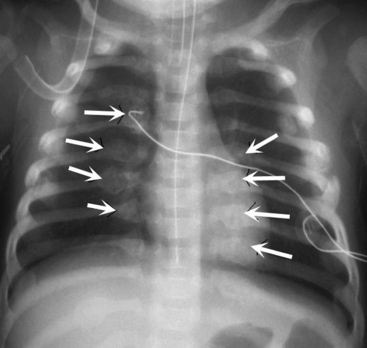

If the film is obtained during expiration, the heart will appear larger and less well defined. The lung fields will appear to be hazier and the pulmonary vascular markings more prominent. Hypoinflation of the lung fields can lead to misinterpretation of the images and misdiagnosis of a basilar pneumonia or cardiomegaly. Furthermore, if maximal inspiration is not present, the lungs can appear more congested and the trachea will appear to buckle to the right.21,24 Figure 10-2 illustrates these differences with two views obtained from a normal child during inspiration and expiration.

image

Fig. 10-2 Inspiratory and expiratory chest radiograph. Normal chest films obtained from the same child during inspiration and expiration. A, Inspiratory phase. Nine ribs can be counted above the diaphragm, indicating good inspiration. Alignment is good (note similarity of clavicles). Penetration of film is good (all vertebral bodies are visible; some pulmonary vascular markings can be seen). Intercostal spaces are equal; both sides of the diaphragm are visible. The mediastinum and trachea are straight (arrows). Heart borders are sharply defined, and heart size is normal. Pulmonary vascular markings are visible in the proximal two thirds of lung fields (normal). B, Expiratory phase. Only eight ribs are visible above the diaphragm (see numbers on ribs), indicating inadequate lung expansion. Alignment is good. Penetration of film is good. Intercostal spaces are narrow because expiration is occurring. Both sides of the diaphragm are hazy, and the left hemidiaphragm is not readily identifiable. The mediastinum appears widened, and the trachea seems to buckle to the right (arrows). Heart appears much larger than in A, and the heart borders are obliterated, but this is caused by expiration and reduction in apparent lung volume. Silhouette sign appears to be present, cardiothoracic size calculated from this view would be large, and pulmonary vascular markings appear prominent, but these are all artifacts caused by expiration.

(Courtesy H. Rex Gardner, Rush Presbyterian Saint Luke’s Hospital, Chicago, IL.)

Examine the bony thorax and the shape of the chest. Infants and young children normally have round chests with a horizontal orientation of their ribs (see Fig. 10-2). However, older children and adults have chests that are wider than they are deep, and their ribs angle downward from back to front. A round chest in an older child or adult is abnormal and may be the result of chronic respiratory disease with air trapping. As discussed, nine or ten ribs should appear above the dome of the diaphragm if a good inspiratory film has been obtained.